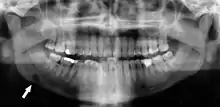

Minimally-displaced fracture in right mandibular. Arrow marks fracture, root canal on central incisor, teeth to the left of fracture do not touch